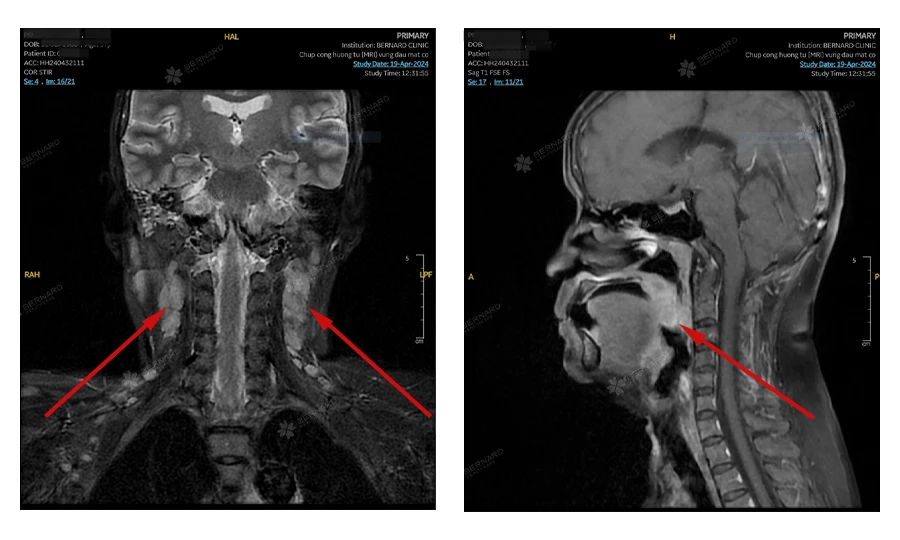

Giai đoạn III - Ung thư lan sang hai bên cổ hoặc cấu trúc sâu hơn

Giai đoạn này cho thấy mức độ xâm lấn đã nghiêm trọng hơn. Tế bào ung thư vòm họng có thể đã phát triển chủ yếu to về kích thước, có thể gây chèn ép dây thần kinh sọ, hạ họng, tuyến nước bọt chính,... hay xâm lấn đến sàn sọ, xương, mô mềm hoặc hốc mắt.

- Xâm lấn xương nền sọ, mô mềm sâu và các xoang vùng mặt (xoang bướm, xoang hàm, xoang sàng…).

Giai đoạn IV - Ung thư lan rộng (di căn)

- Xâm lấn các mô quan trọng vùng đầu mặt cổ

Ung thư đã xâm nhập vào các cấu trúc sâu, bao gồm: Xương nền sọ, xương cổ, cơ hàm, các xoang quanh mũi và mắt (xoang cạnh mũi, xoang trán, xoang bướm...). Đồng thời có thể đã lan sang các hạch ở cổ hoặc sau họng, với kích thước ≤ 6cm.